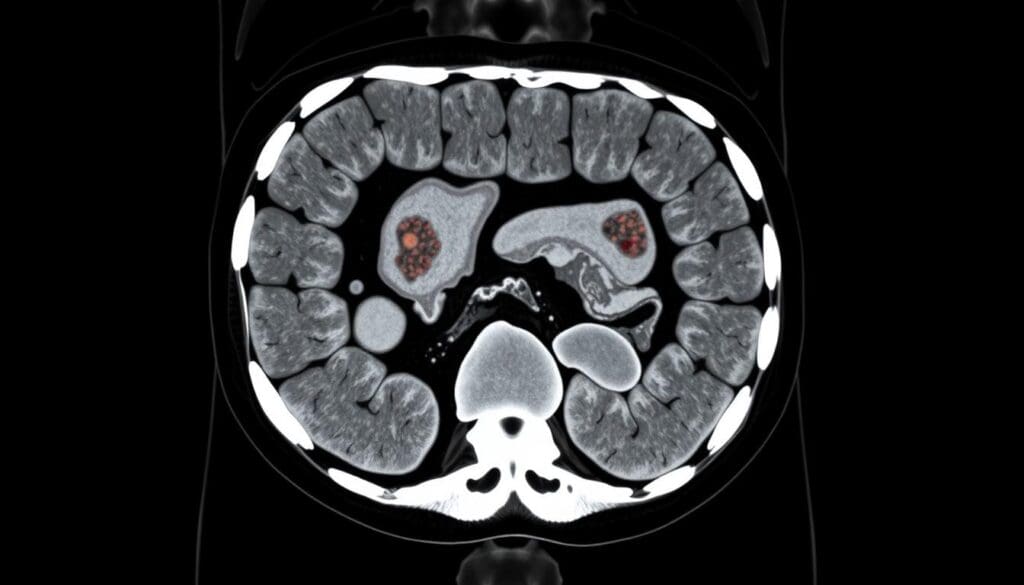

Finding colon cancer early is key to treating it well. Modern CT scans help doctors spot tumors and see if they’ve spread. This is important for treating the cancer right.

CT scans make detailed pictures of the belly and pelvis. Doctors use these to understand symptoms, know how far the cancer has spread, and check if it comes back. Even though they’re not the first choice for screening, CT scans are great for seeing how big the cancer is.

CT scans are good at finding colon cancer, but how well they do depends on the tumor size and the technology used. They are key in finding and understanding colorectal cancer.

Detection Rates and Sensitivity Percentages

Research shows CT scans can spot colorectal tumors with varying success. They are best at finding big tumors, with success rates from 76 to 100 percent for tumors over 10 mm. For tumors bigger than 2 cm, they are even more accurate, spotting them 85-95% of the time.

A study in the Journal of Clinical Gastroenterology found that CT scans are very good at finding colorectal cancers, but they work best for bigger tumors.

“The sensitivity of CT colonography for detecting colorectal cancer was 96% for cancers 2 cm or larger.”

Accuracy in Different Stages of Colorectal Cancer

CT scans work differently at different stages of colorectal cancer. They are very good at finding advanced stages, but not as good for early stages or small polyps. For very early lesions, they are less than 40% accurate.